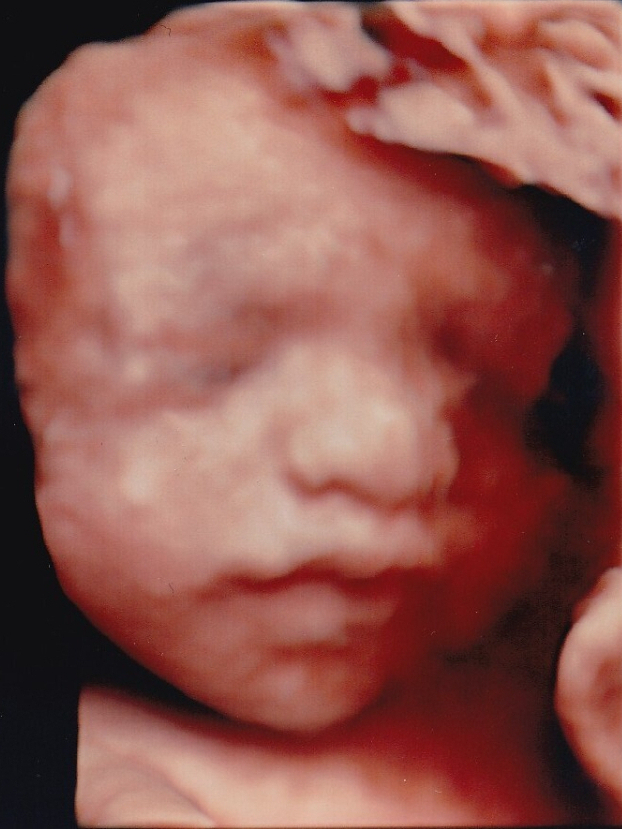

妊婦健診時の赤ちゃんの超音波画像記録について(ベビー動画館)

ご希望の方には「ベビー動画館」アプリをご利用いただき、お一人様ごと専用IDにてスマートフォンからいつでも健診動画をみることができます。